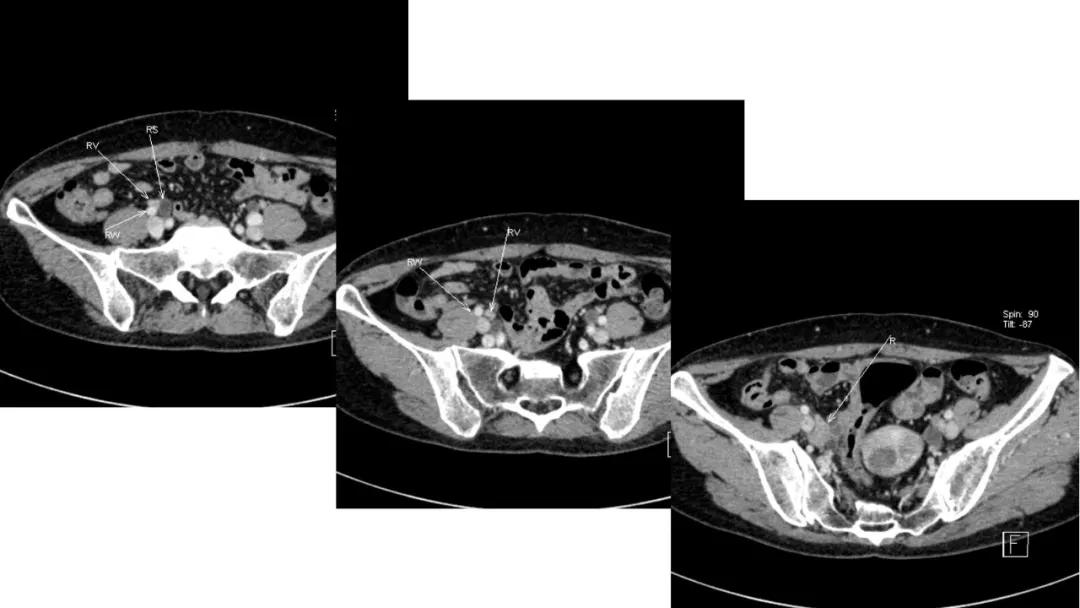

病理:子宫肌瘤粘液样变性

病例4 女,32岁,以“月经量增多伴经期延长半年。”

缘于患者入院前半年无明显诱因出现月经量增多,卫生巾由原来3包余增至5包不等,伴血块,经期由原来7天延长至10-15天不等,无痛经,无月经周期改变,无阴道异常排液,无畏冷、发热,无头晕、乏力等不适,未重视,未诊治。期间症状持续。2月前就诊我院,查彩超示:“子宫体大小约5.7*5.3*4.6cm,内膜厚约0.6cm,回声不均,左卵巢旁探及大小约4.2*3.5cm低回声区。”建议治疗,患者及家属表示考虑。期间症状持续,今就诊我科门诊,要求住院手术治疗,无腹痛等不适,门诊拟“卵巢囊肿”收住入院。既往史:2007年剖宫产一次,术顺。月经史:15 7/25 lmp2018.05.14,量中,无痛经。婚育史:已婚,1-0-3-1,末孕2007年剖宫产娩一男婴,儿子及丈夫体健。个人史、家族史均无特殊。

CA125 335.5(U/mL);2018-05-30 彩超:子宫宫体大小约5.6㎝×6.3㎝×4.9㎝,形态正常,宫壁回声欠均,内膜厚约1.8cm,回声不均。CDFI:子宫内未见明显异常彩色血流信号。左附件区探及一混合回声团块,大小约9.8㎝×7.9㎝,CDFI:其实性部分可见少许彩色血流信号。右附件区未见明显包块回声。

病理:卵巢子宫内膜样癌